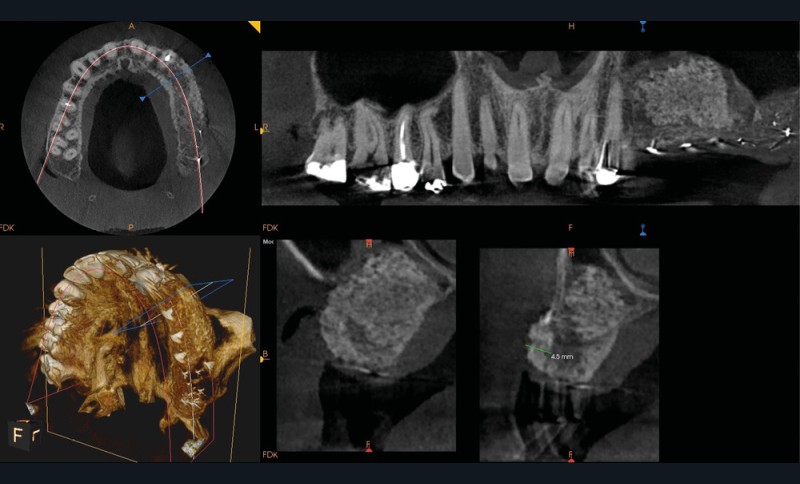

Patient de 55 ans adressé pour une augmentation de volume osseux dans le secteur maxillaire postérieur gauche.

L’augmentation osseuse est réalisée grâce à un comblement sous-sinusien au niveau du maxillaire gauche, associé

à une Régénération Osseuse Guidée (ROG), cela lors de la même chirurgie dénommée « Hamac Technique ».